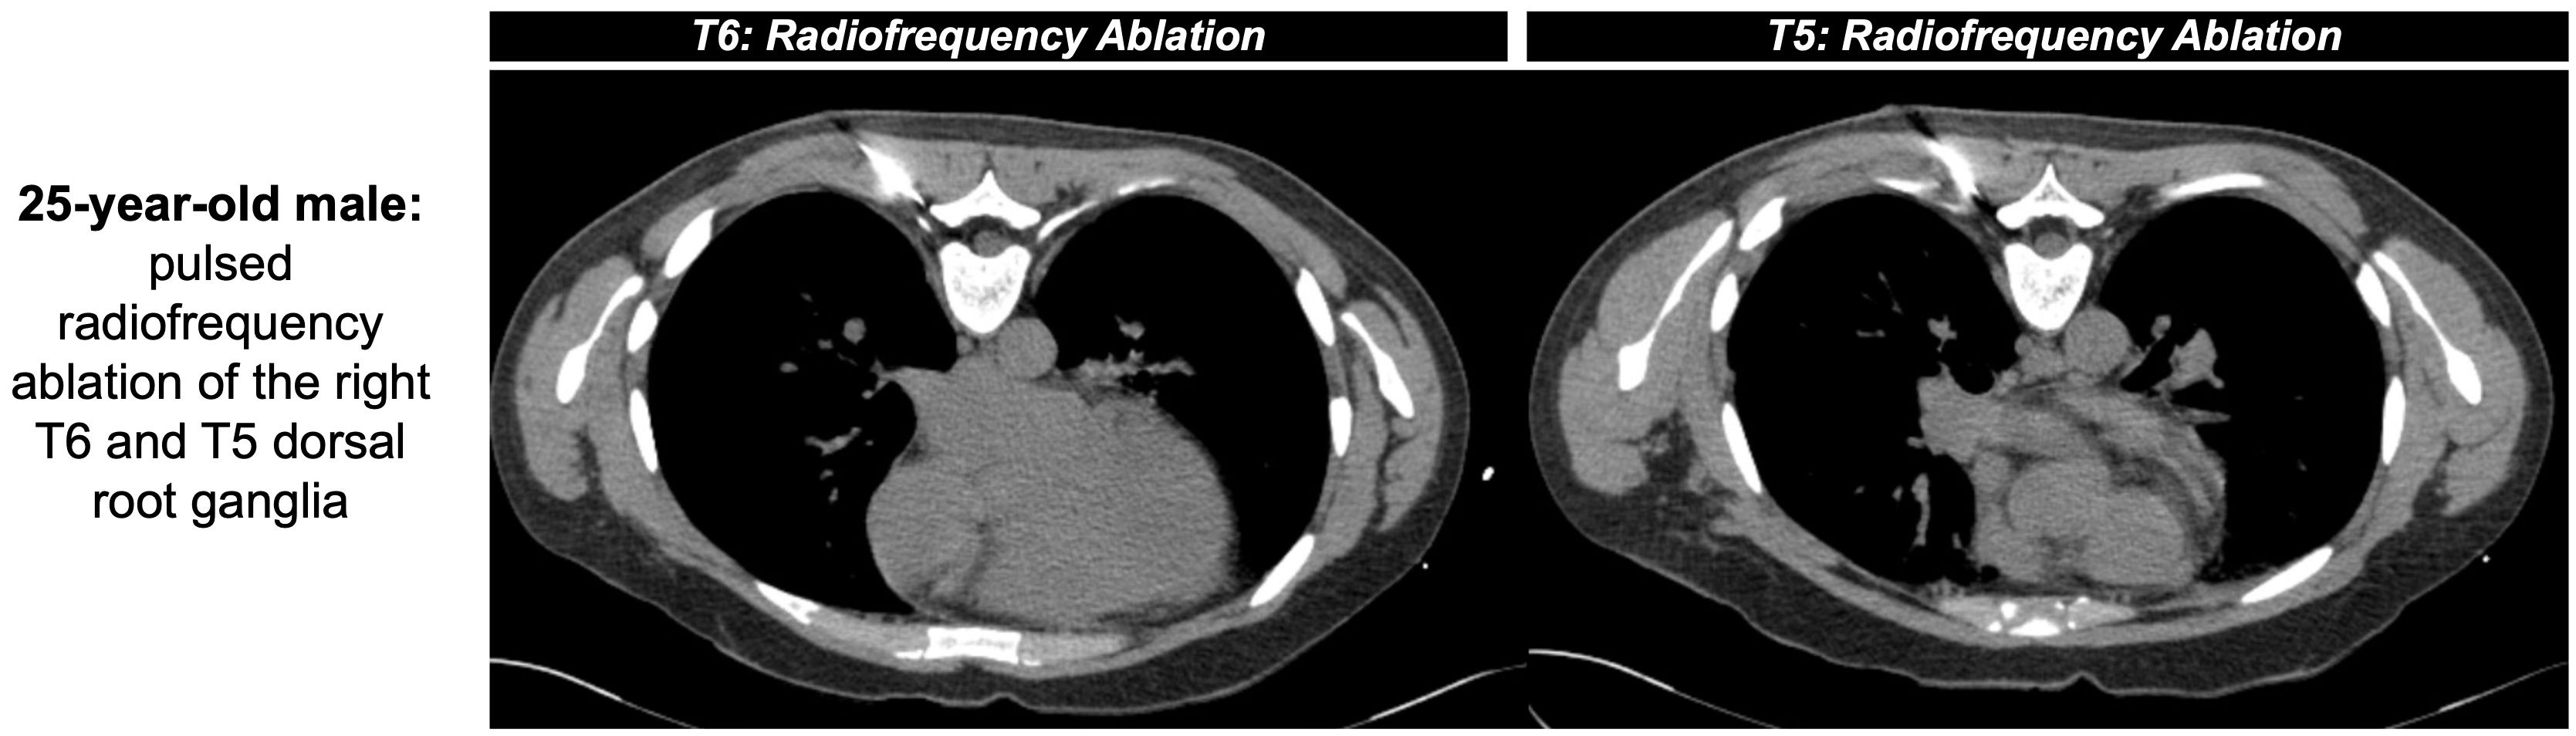

Akin to the niche interventionalists can fill via nerve blockades, nerve ablation serves as an additional method for longer control of cancer-related pain. As described above, pain in systemic conditions like MM is multifactorial and related to the release of pro-inflammatory cytokines, nerve infiltration of bone marrow, and stimulation of afferent nerves (51). Nerve ablation causes degeneration of sensory fibers and accompanying myelin sheaths distal to the lesion, known as Wallerian degeneration, leading to a temporary halt of nerve signal transmission. This process can be achieved via either chemical or thermal ablation, with the latter including conventional RFA, though RFA may have faster recurrence and is more time consuming than chemical denervation via alcohol (52) (Figure 3). The temporary disruption and subsequent potential for peripheral axonal regeneration can be attributed to the preservation of Schwann cells, but the risk of recurrence may be diminished with a larger distance between the proximal axonal stump and distal fibers (52, 53). To achieve the greatest success with pain management, ablative techniques like RFA must target the bone-tumor interface for substantial destruction of nerve endings in addition to addressing the mass itself (54). However, research on nerve ablation in the MM patient population is limited, with some studies suggesting there is no significant difference between pain relief achieved via RFA from neural destruction and decreased cytokine production versus vertebroplasty with stabilized trabecular bone (31).

Figure 3. 25-year-old male with intractable herpatic neuralgia at the level of T6 presented for CT-guided RFA (shown as an example of nerve ablation non-specific to MM). Pulsed RFA was applied (42 °C for 2 minutes at a frequency of 2 hertz, 60 volts, impedance between 200 and 500 ohms) outside both the right T5 and T6 neural foramina. An additional lesion was created near T6 via conventional RFA (80 °C for 90 seconds) before removal of instruments with positive post-operative outcomes.